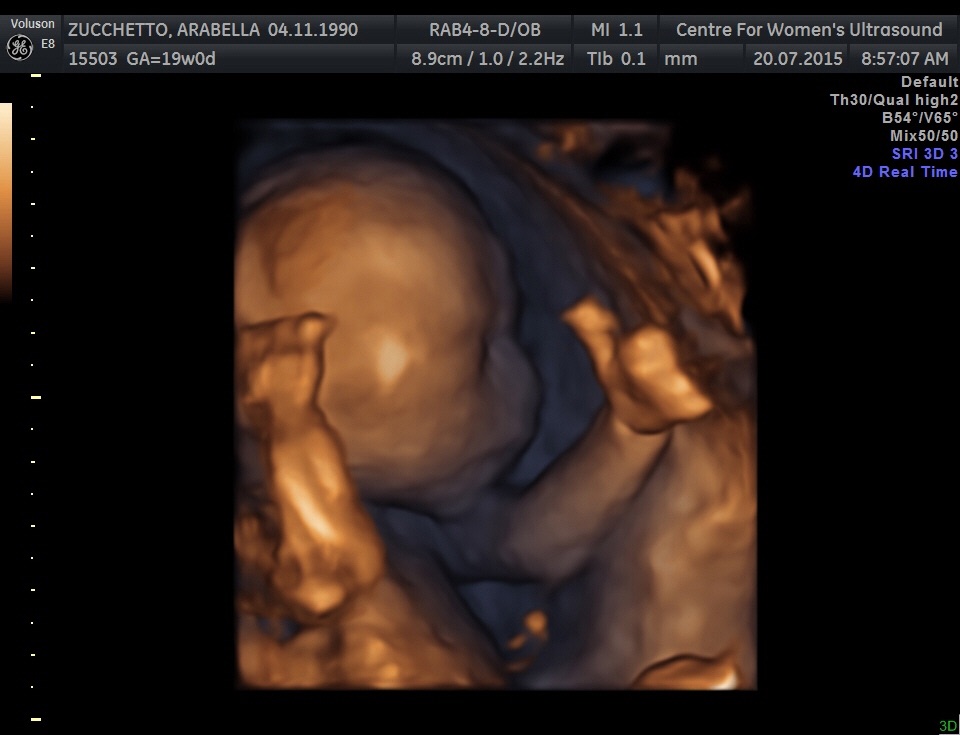

Had mine 7/9/15 @ 19 weeks exactly. My perinatologist was particularly looking for any heart defects and abnormalities in the kidneys or urinary tract--my little girl has a single umbilical artery (SUA; aka "two-vessel cord) and this abnormality has been correlated with abnormalities in these two organ systems. They did the fetal echo in conjunction with the anatomy scan and my perinatologist said everything looked great. This was my main concern so I feel as though a huge weight has been lifted. I was on the US table for over two hours so that she could get sonogram "video" of the heart and look at the kidneys more in depth too so it was definitely my longest US to date. We knew the sex was a girl from a prior 15w scan but it was confirmed again. She is measuring in the 33rd percentile, and we conceived 10 days after my last period, not 14, so she is actually likely a bit smaller. This is par for the course for SUA babies so my OB has already informed me we will be getting serial growth scans from here on out, Doppler velocimetry at each visit, as well as NST's weekly or twice weekly starting at 32 weeks (much earlier if she declines in growth percentile). SUA babies--mine LO's is "isolated", meaning it is not associated with a chromosomal abnormality or a organ defect--are at a significantly higher risk for IUGR and even stillbirth, thus the very close monitoring. If she drops below the 10th percentile in terms of growth it will be time to consider delivering via c-section since this would indicate she isn't getting the nutrients she needs due to the cord abnormality and would be "better out than in." My OB said he would likely not let her go past 37 weeks, so my little one could arrive closer to mid-November as opposed to closer to her due date of 12/3. Just seeing a beating 4-chambered heart that is structurally and functionally normal, two kidneys and a normal urinary tract just made my month. Literally.

We knew the sex was a girl from a prior 15w scan but it was confirmed again.

She is measuring in the 33rd percentile, and we conceived 10 days after my last period, not 14, so she is actually likely a bit smaller. This is par for the course for SUA babies so my OB has already informed me we will be getting serial growth scans from here on out, Doppler velocimetry at each visit, as well as NST's weekly or twice weekly starting at 32 weeks (much earlier if she declines in growth percentile). SUA babies--mine LO's is "isolated", meaning it is not associated with a chromosomal abnormality or a organ defect--are at a significantly higher risk for IUGR and even stillbirth, thus the very close monitoring. If she drops below the 10th percentile in terms of growth it will be time to consider delivering via c-section since this would indicate she isn't getting the nutrients she needs due to the cord abnormality and would be "better out than in."

My OB said he would likely not let her go past 37 weeks, so my little one could arrive closer to mid-November as opposed to closer to her due date of 12/3.

Just seeing a beating 4-chambered heart that is structurally and functionally normal, two kidneys and a normal urinary tract just made my month. Literally.